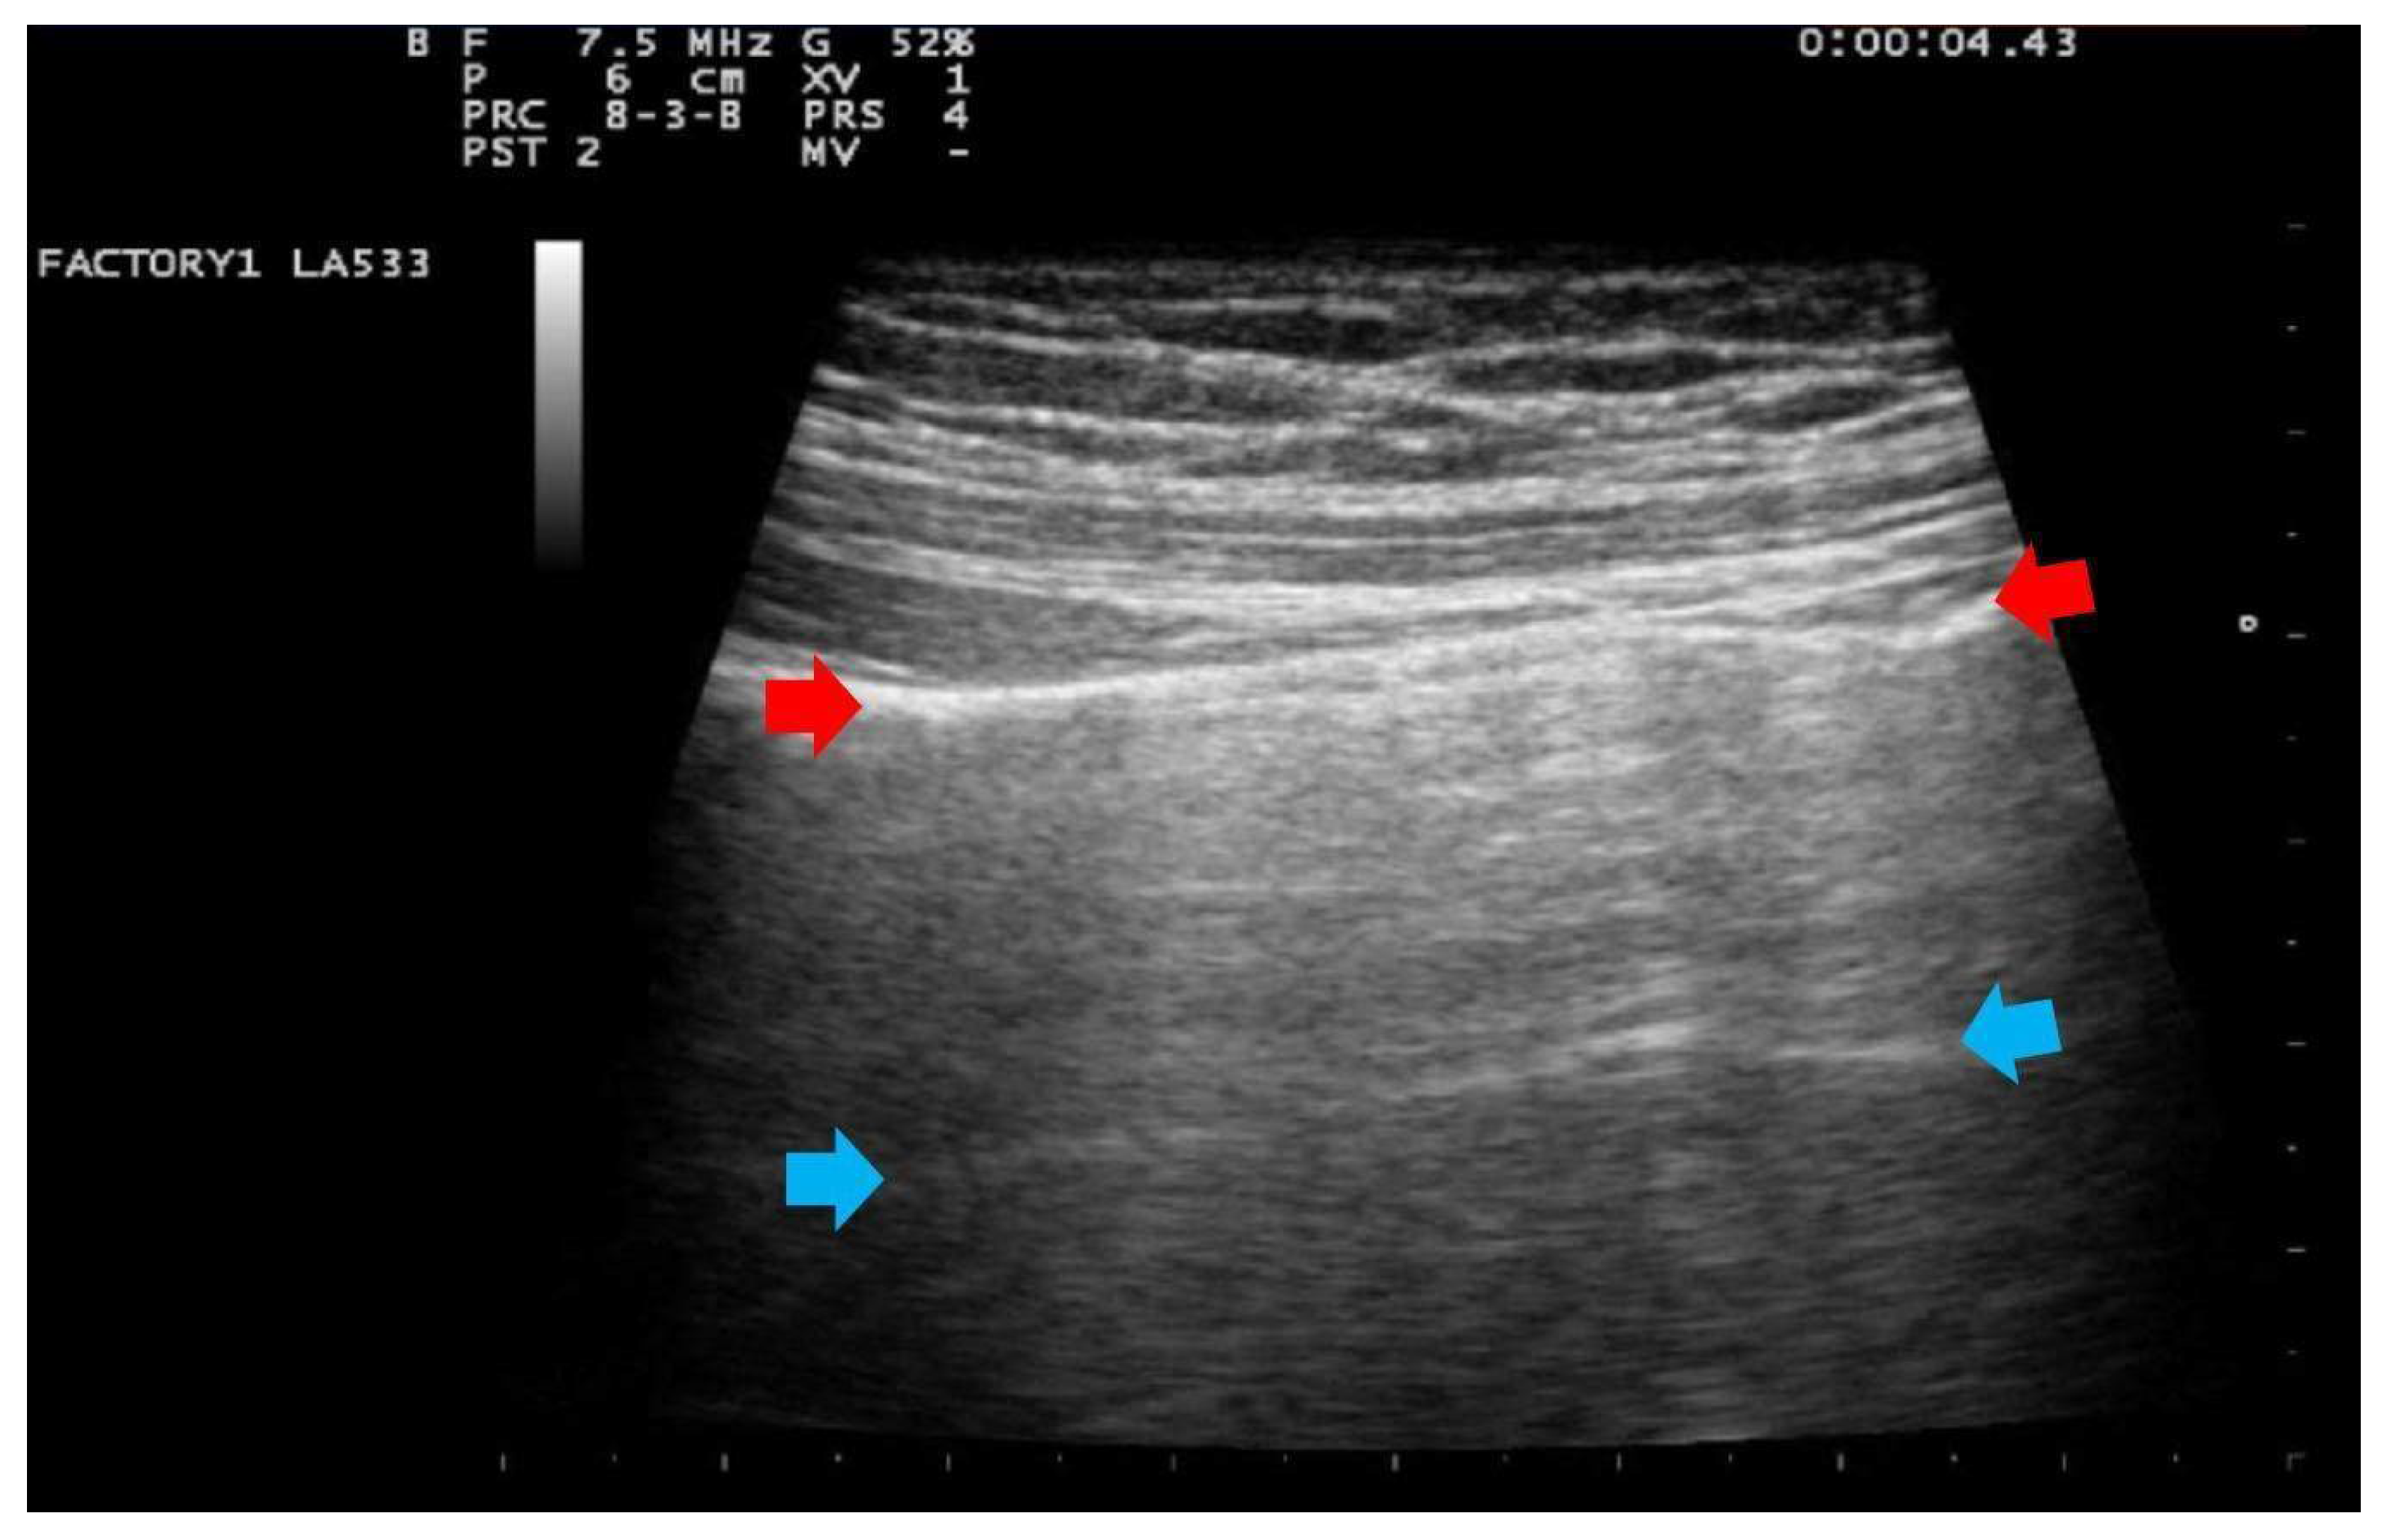

- Score 0:

- predominant A-lines or <3 separated B-lines. (Figure 1)